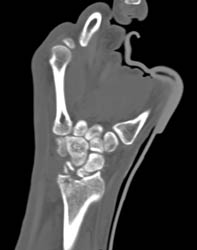

Diagnosis

Tendons- Normal